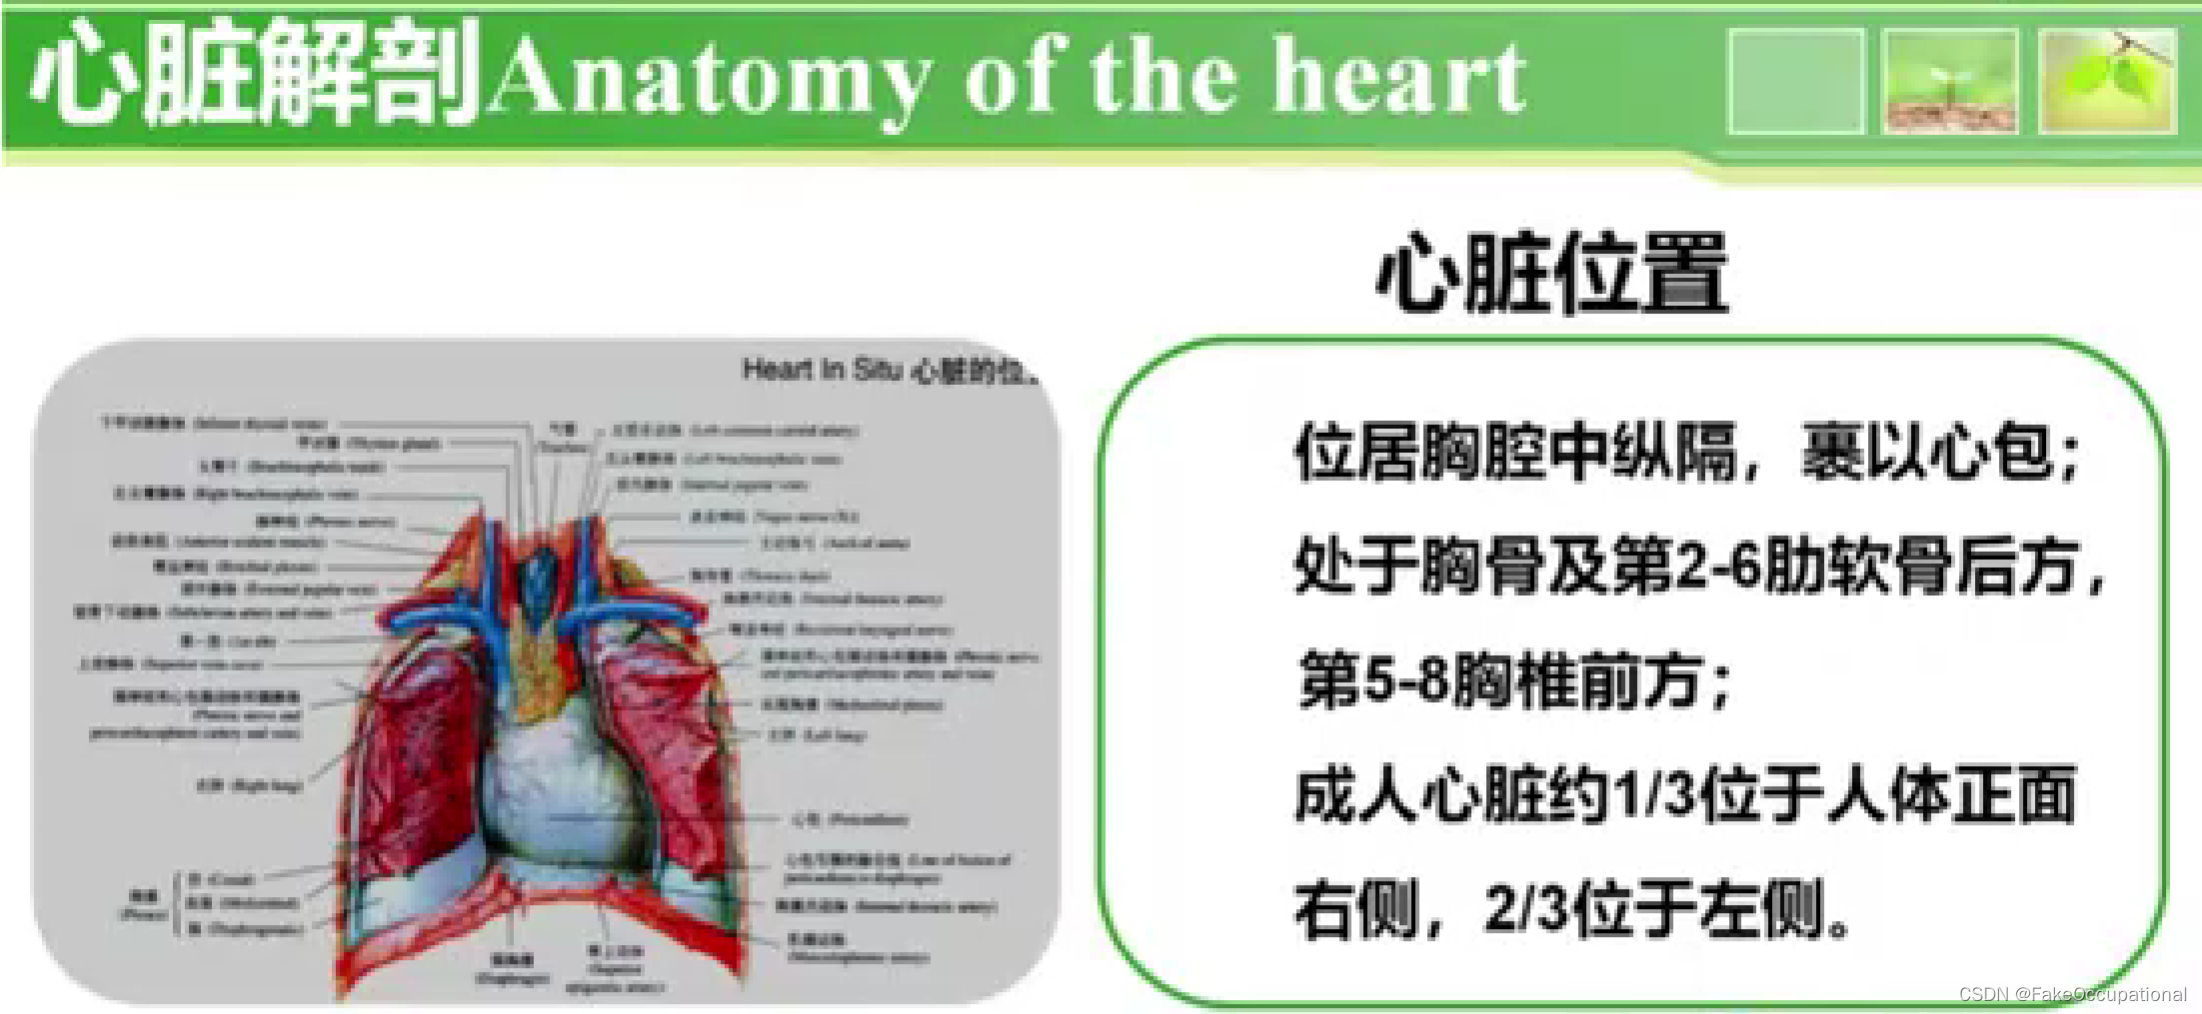

心脏解剖及生理概要